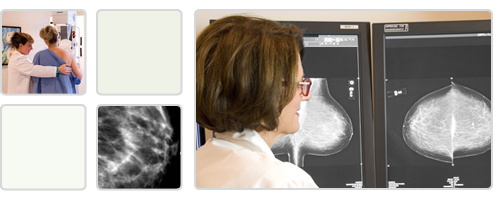

QU'EST-CE QU'UNE MAMMOGRAPHIE? La mammographie est un examen utilisant des rayons-X pour détecter ou diagnostiquer une pathologie du sein. Il s'agit d'un examen sécuritaire qui utilise des doses très faibles de radiation pour produire des images de haute qualité.

QU'EST-CE QU'UNE MAMMOGRAPHIE DIAGNOSTIQUE? La mammographie diagnostique est proposée lorsqu'une patiente est symptomatique (masse ou induration du sein, écoulement, irritation du mamelon) ou lorsqu'une anomalie a été détectée à la mammographie de dépistage.

En plus des 2 images par sein, il est parfois nécessaire d'obtenir des films additionnels d'une région du sein avec agrandissement pour mieux évaluer une anomalie.

Sachez que la majorité des anomalies découvertes à la mammographie sont bénignes et ne représentent pas un cancer du sein. |